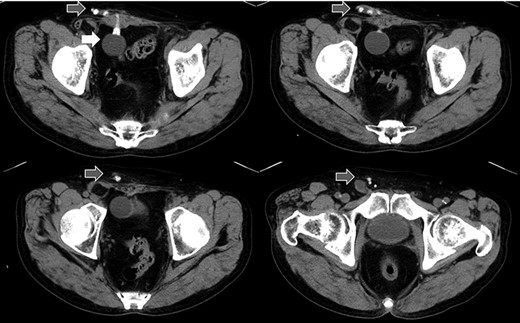

Abdominal CT in Case 2: the balloon was located near the bladder and the tube went through rectus abdominis muscle; balloon, white arrow; tubes, gray arrows.

A 75-year-old male was referred for the treatment of a right IH. He also had received AUS implantation for a similar medical course. Abdominal CT demonstrated that a balloon was located beside the bladder and that the connecting catheter went through the rectus abdominis muscle and reached to the right scrotum through the subcutaneous layer (Fig. 5). The catheter was palpable subcutaneously; therefore, skin incision was placed on the outer site rather than in the normal situation. The diagnosis was indirect hernia and we did not observe any components of the AUS in the inguinal canal and repaired it using the Lichtenstein method.